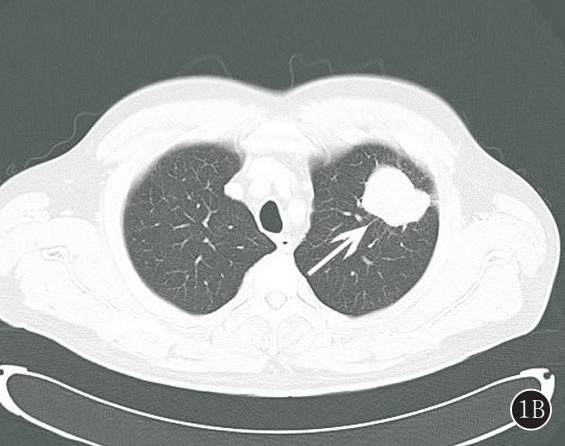

图 2A,B 右下肺纤维肉瘤。 A. 肿块密度不均匀,边缘见分叶征,局部与邻近胸膜关系密切;B. 肿瘤由单一的异型梭形细胞组成,细胞呈较规则的束状排列(HE ×100)